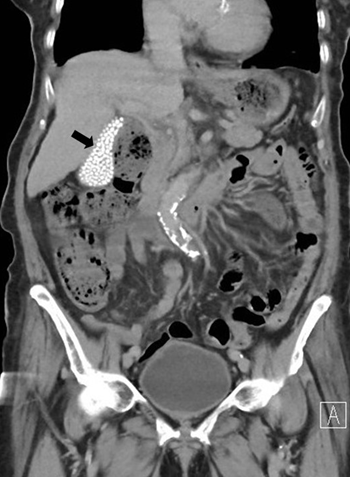

A 91-year-old woman presented with right flank pain for two days without fever, dysuria, trauma, or recent falls. Physical examination revealed no costovertebral angle tenderness. Laboratory tests showed an elevated C-reactive protein level of 3.6 mg/dL without leukocytosis. Urinalysis demonstrated pyuria and bacteriuria. She was treated empirically for acute pyelonephritis with intravenous cefoxitin, and urine culture later grew Escherichia coli sensitive to cephalosporins. Abdominal computed tomography (CT) revealed rupture of a right renal cyst. Incidentally, the gallbladder was filled with multiple small, round, hyperdense calculi, producing a striking "bag of stones" appearance (image 1, arrow). These findings were consistent with asymptomatic cholelithiasis. The patient´s flank pain improved after a 7-day course of antibiotics. She was discharged in stable condition, and outpatient follow-up was unremarkable. Asymptomatic gallstones are commonly detected incidentally, and most patients remain symptom-free; therefore, expectant management is generally recommended. Prophylactic cholecystectomy is reserved for selected high-risk patients, such as those with porcelain gallbladder, large gallstones (>3 cm), anomalous pancreaticobiliary ductal junctions, gallbladder adenomas, or underlying hemolytic disorders.